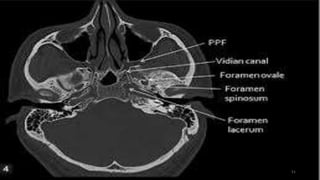

Vidian canal

Foramen ovale

Foramen spinosum

VIDIAN CANAL-Pterygoid canal